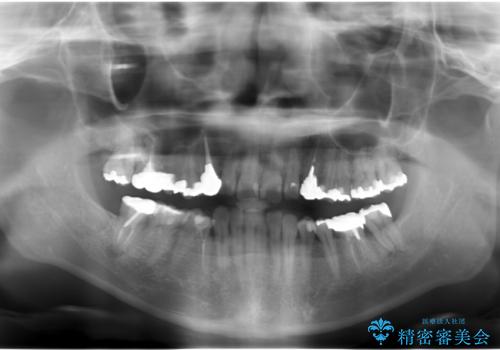

- 長年虫歯の治療を受け続けたことで銀歯・コンポジットレジン修復だらけになってしまい、今後の見た目や歯を大切にするためにセラミック治療矯正治療を希望され来院されました。

マイクロスコープを用いた精密根管治療やセラミック治療、マウスピース矯正治療を一つの医院で行うことのできる当法人ならではの総合歯科治療を実践していきます。